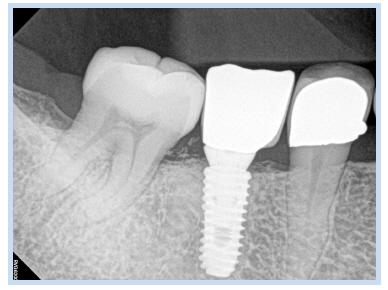

37세 여성이 오래 전에 발거한 하악 우측 제1대구치 위치의 무치악 부위 임플란트 식립 및 수복을 위하여 내원하였다. 파노라마 방사선 사진에서 하악 우측 제1대구치를 발치한 무치악 부위에 방사선 불투과상을 보이는 잔존 치근으로 추정되는 것이 관찰되었다(Fig. 13). 잔존 치근은 그대로 남겨둔 채로 임플란트를 식립하기로 계획하였다. 국소마취하에 치조정 절개 및 골 점막 피판을 거상하여 직경 4.5 mm 높이 10 mm의 임플란트를 식립하였다. 치유 지대주를 연결한 후 fixture의 근심 면의 협측에 골열개가 존재하여 분말형 자가치아골이식재를 이식하였다. 피판을 재위치시키고 4-0 Vicryl로 봉합하였다. 1주 후 봉합사를 제거하였고 치근단 방사선 사진을 촬영하였다(Fig. 14). 임플란트 식립 3개월 후에 최종 보철물을 장착하였고, 임플란트 식립 5개월 후 근심 측 식편압입을 호소하여 보철물을 다시 제작하여 장착하였다. 임플란트 식립 47개월 후에 촬영한 치근단 방사선 사진을 통해 안정적으로 임플란트가 유지되고 있음을 관찰할 수 있었다(Fig. 15, 16).

Fig. 15. Follow-up periapical radiograph. (A) Periapical radiograph 6 months after implant placement. (B) Periapical radiograph 12 months after implant placement. (C) Periapical radiograph 27 months after implant placement.

Jun-Bae Sohn et al. : Implant Placed in Contact with Retained Root: Case Reports. Implantology 2016